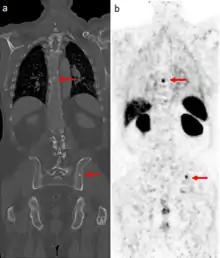

Gallium-68 DOTA scans are increasingly replacing octreotide scans (a type of indium-111 scan using octreotide as a somatostatin receptor ligand). The gallium-68 is bound to an octreotide derivative chemical such as DOTATOC and the positrons it emits are imaged by PET-CT scan. Such scans are useful in locating neuroendocrine tumors and pancreatic cancer.[7][8]

Gallium DOTA scans

68Ga DOTA conjugated peptides (including 68Ga DOTA-TATE, DOTA-TOC and DOTA-NOC) are used in positron emission tomography (PET) imaging of neuroendocrine tumours (NETs). The scan is similar to the SPECT octreotide scan in that an octreotide-based somatostatin analogue (such as edotreotide) is used as the radioligand, and there are similar indications and uses as ocreotide scans, however image quality is significantly improved.[35] Somatostatin receptors are overexpressed in many NETs, so that the 68Ga DOTA conjugated peptide is preferentially taken up in these locations, and visualised on the scan.[36] As well as diagnosis and staging of NETs, 68Ga DOTA conjugated peptide imaging may be used for planning and dosimetry in preparation for lutetium-177 or yttrium-90 DOTA therapy.[37][38]